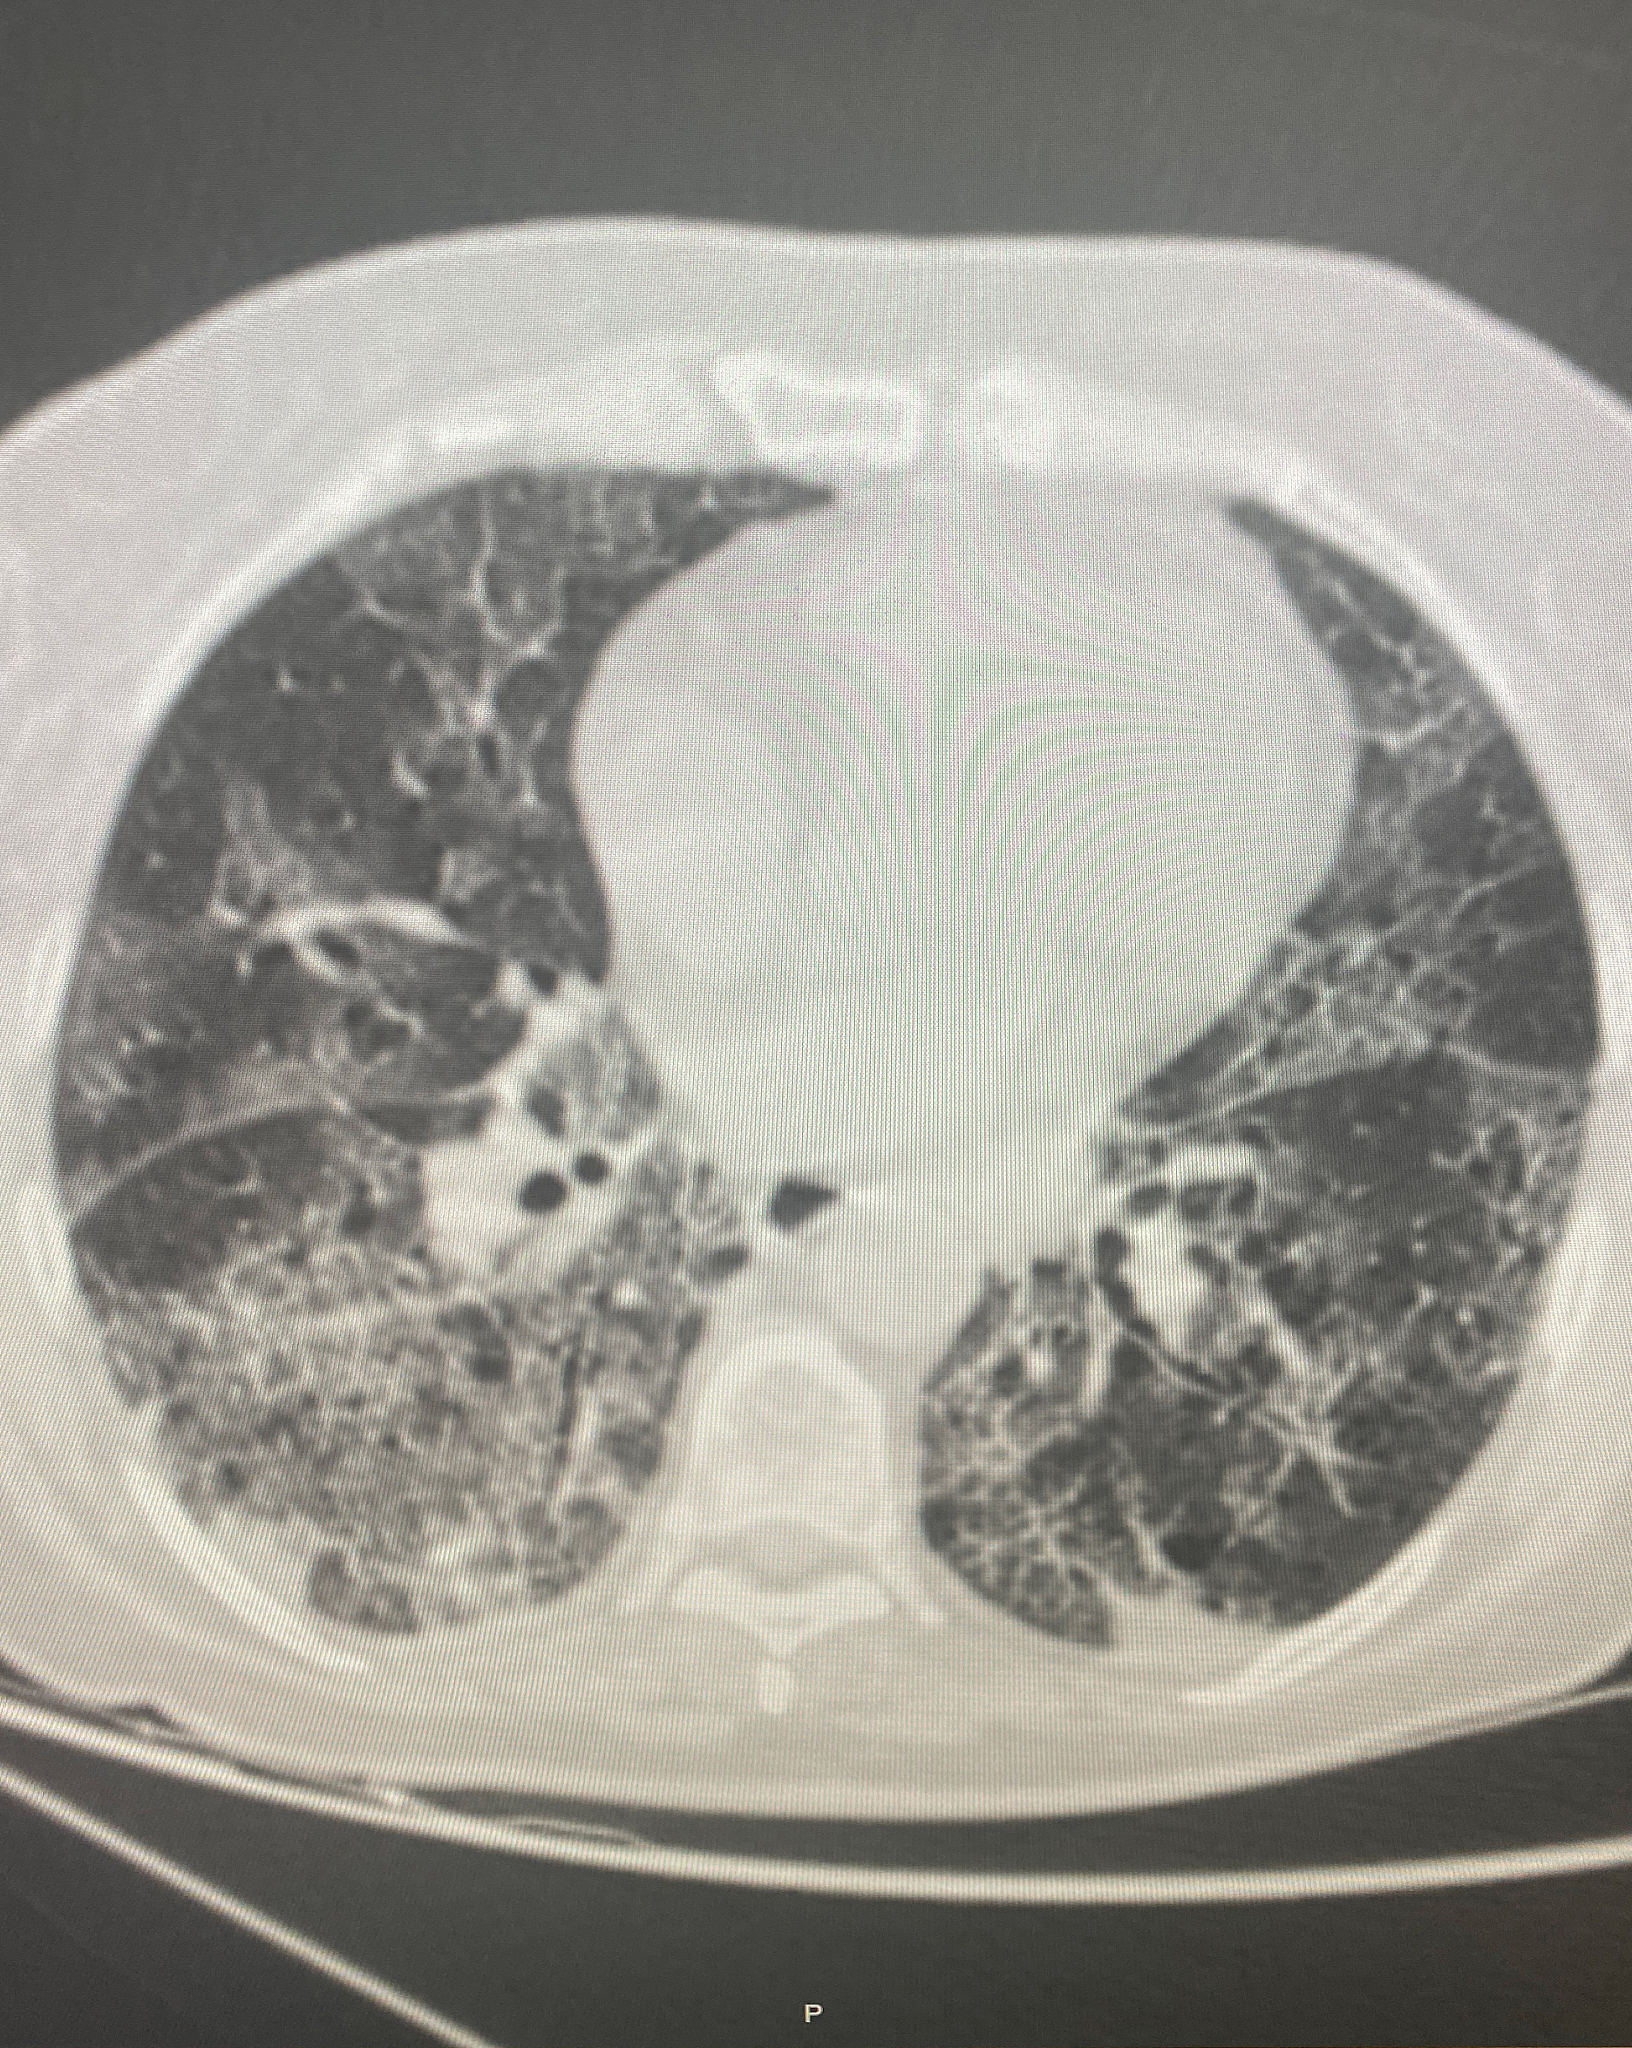

给以下文案写一个标题党的标题现在啊随着薄层CT的普及和大家对于体检的重视发现肺结节的患者越来越多了那什么样的肺结节需要手术呢?简单来说啊就是当怀疑肺部小结节可能是恶性病变的时候就要考虑进行手术了。临床上通过判断肺小结节的大小和密度来区分良恶性。首先让我们来谈谈结节的密度不同密度的肺小结节有不同的恶性概率。根据结节的密度可以将肺结节分为实性结节、部分实性结节和磨玻璃密度结节。其中部分实性结节的恶性概